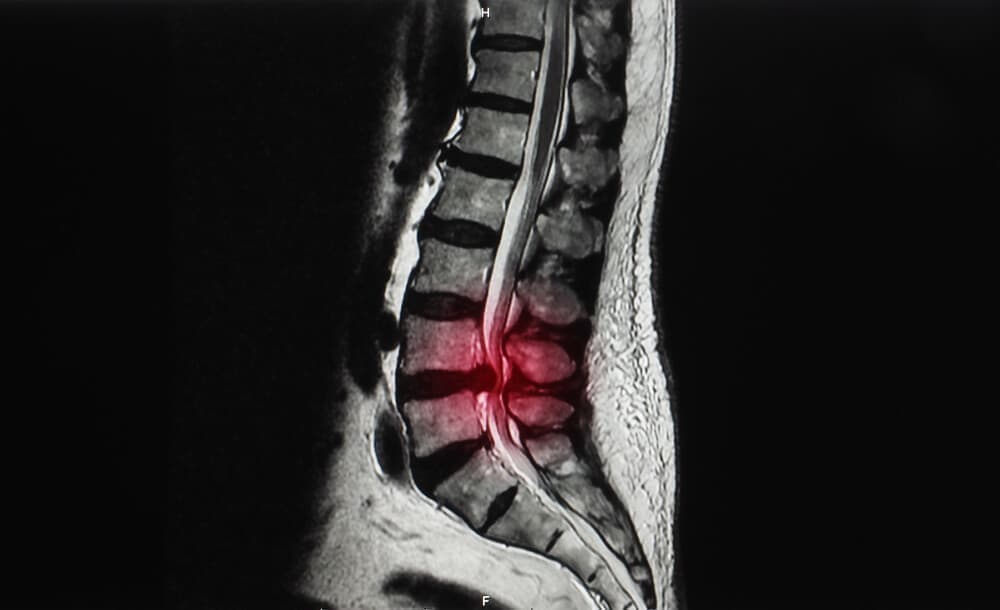

腰椎すべり症とは?

背骨(脊柱)にある椎骨という骨にズレが生じている状態のことを腰椎すべり症と呼ばれています。

背骨(脊柱)は、椎骨がいくつも連結して形成されています。

すべりが生じることにより腰椎が安定せず、神経が通っている脊柱管が狭窄して神経に圧力を与えます。